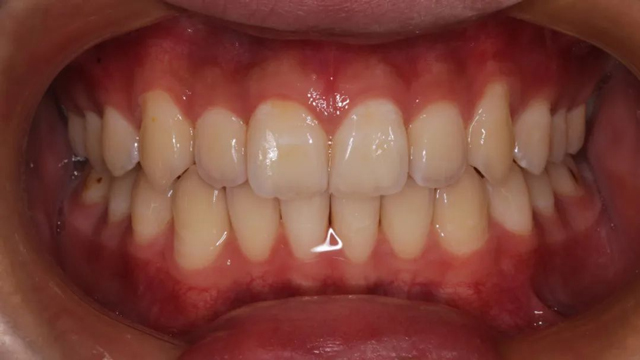

2021年8月(矯正前口內(nèi)照)

這位小患者的口腔問(wèn)題包括:牙列不齊,個(gè)別門牙反頜,左上尖牙完全埋伏阻生,另外,CBCT顯示右上門牙牙根腭側(cè)內(nèi)還有一顆多生牙。

簡(jiǎn)單地說(shuō),牙齒不整齊只是小問(wèn)題,他更大的問(wèn)題是:在不該長(zhǎng)牙的地方多長(zhǎng)了一顆牙,而乳尖牙滯留,早該替換出來(lái)的尖牙長(zhǎng)不出來(lái),這兩顆牙的問(wèn)題如果不及時(shí)干預(yù)治療,會(huì)帶來(lái)很多長(zhǎng)期的口腔問(wèn)題。